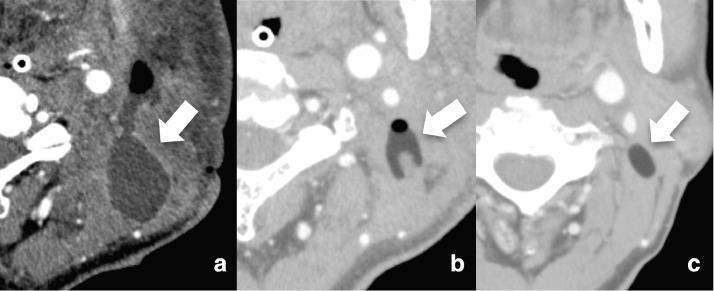

Antibiotic ointments are often used to treat or prevent infections in surgical wounds. However, due to a dearth of reports on adverse effects, the complications of the use of such ointments, especially possible long-term effects, are largely unknown. We experienced a unique case of a cystic lesion that developed after surgical site infection treated with gentamicin ointment in a 62-year-old man who underwent subtotal glossectomy for tongue cancer. The antibiotic ointment that was applied following abscess drainage remained there, replacing the abscess cavity and forming an oval mass. The lesion was found incidentally on follow-up MR examination to monitor cancer recurrence. On both T1- and T2-weighted images, it showed high-intensity reflecting oily base material, constituting the ointment, which appeared to be a fat-containing tumor such as a lipoma that had arisen at the surgical site. Echo-guided drainage extracted the ointment, which was seemingly unaltered from the time it was applied 11 months before. We describe the clinical course and imaging findings to acknowledge this potential adverse effect associated with topical antibiotic treatment for surgical site infection.

抗生素软膏常用于治疗或预防手术伤口感染。然而,由于关于不良反应的报道较少,此类软膏使用的并发症,尤其是可能的长期影响,在很大程度上尚不明确。我们遇到了一例独特的囊性病变病例,该病例发生在一名62岁因舌癌接受舌次全切除术的男性患者身上,其手术部位感染后用庆大霉素软膏治疗。脓肿引流后涂抹的抗生素软膏留在了原处,取代了脓肿腔并形成了一个椭圆形肿块。该病变是在随访磁共振检查以监测癌症复发时偶然发现的。在T1加权和T2加权图像上,它均显示出高强度信号,反映了构成软膏的油性基质,看起来像是手术部位出现的含脂肪肿瘤,如脂肪瘤。超声引导下引流抽出了软膏,其外观与11个月前涂抹时似乎没有变化。我们描述了该临床过程和影像学表现,以认识到这种与手术部位感染局部抗生素治疗相关的潜在不良反应。